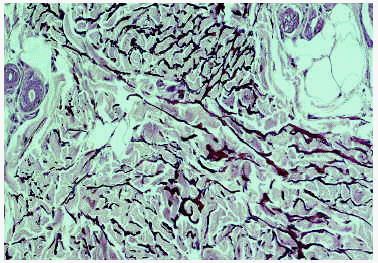

Un estudio radiológico de serie ósea identificó numerosas lesiones esclerosas redondeadas, de bordes bien definidos, localizadas en metatarso, metacarpo, falanges (fig. 3) y epífisis de tibia y peroné, sin afectación cortical, compatibles con lesiones de osteopoiquilia. Los padres del paciente no mostraban alteraciones cutáneas y no se han realizado estudios radiológicos.

Fig. 3.--Lesiones osteoscleróticas en el carpo, metacarpo y falanges.

Las lesiones de osteopoiquilia son osteoscleróticas que se revelan desde el punto de vista radiológico como unas condensaciones esféricas en epífisis y metáfisis de los huesos largos, pelvis, manos y pies10. Representan una alteración estructural sin limitación funcional y por lo tanto sin repercusión clínica11. La osteopoiquilia se descubre en muchos casos como un hallazgo casual en el examen radiológico tras un traumatismo. Se desarrolla lentamente y no se suele detectar hasta la adolescencia, aunque en algunas ocasiones, como en nuestro caso, las manifestaciones óseas se pueden observar a edad temprana11. Se han descrito otras manifestaciones óseas asociadas como exostosis, encondromas y osteofibromas12. Se han descrito casos en familiares de pacientes con síndrome de Buschke-Ollendorf que presentaban lesiones de osteopoiquilia sin lesiones cutáneas o viceversa7.